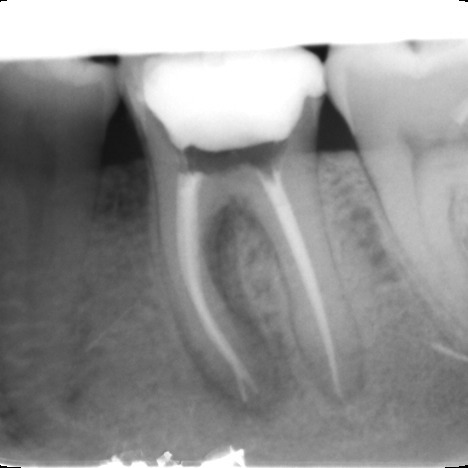

Files of different sizes are used to eliminate bacteria and infection and to shape the canals. The canals are disinfected thoroughly with irrigants and later the canals will be sealed in 3 dimensions with a special medicament called gutta-percha to prevent reinfection of the tooth and the access cavity will be sealed with a temporary filling.

After a few weeks, the tooth will be checked and when all the infection has cleared, a crown will be usually required to protect the restore the tooth to function.